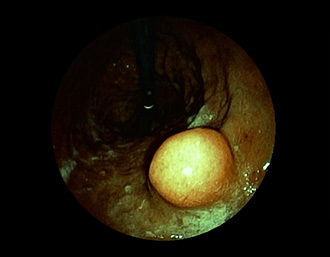

症例5:胃腺腫(84才女性)

胃角部に、大きさ10mm強のなだらかな粘膜隆起を認める。生検:Tubularadenoma with moderate atypia.Group 3。経過観察中。

(FICE画像)